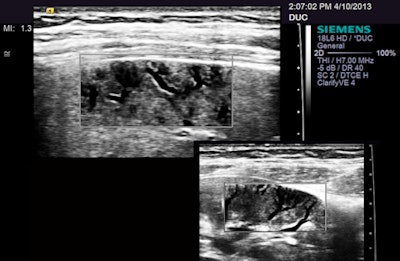

I was really intrigued by one new feature on the S3000 that was billed as a way of cleaning up images. Called Clarify, this seems to be a form of power Doppler that displays flow as black, subtracting intravascular movement from the image -- a kind of blacklight viewing. In any case, this has potential for exposing small peripheral vessels without the color blooming that often wipes out detail in energy and power Doppler usage, especially when filters are set for maximal sensitivity.